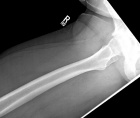

46 year old male noted some fullness in his right thigh about 5 months prior to presentation. Noticed some tense feelings in his thigh over the past month.

Zoom image: Radiological image Radiological image.